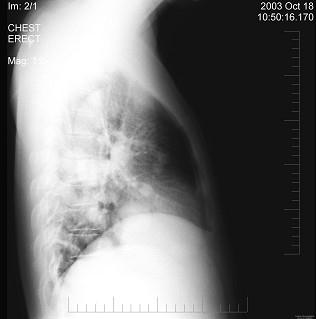

问题 男性,43岁,胸闷、胸痛10余天,不咳嗽不发热,X线检查如图,最合理的诊断是 ( )

选项 A.原发性肺癌 B.肺转移瘤 C.炎性假瘤 D.结核瘤 E.支气管扩张

答案 B